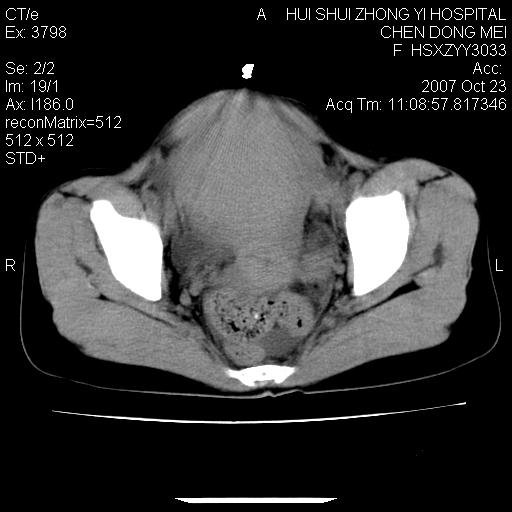

标题: CT10156:女.43岁,发现中下腹部包都块2年 [打印本页]

标题: CT10156:女.43岁,发现中下腹部包都块2年

发现中下腹部包都块2年。2年来月经不规律。

腹腔巨大软组织密度影,边缘光滑,包膜完整,内囊变坏死。腹膜后及盆腔内淋巴结肿大。结合病史考虑卵巢癌可能性大。

病灶内可见脂肪密度影,考虑畸胎瘤可能性大

病变巨大,呈囊实性改变,包膜较厚且完整,内见分膈,周围脏器明显受压移位,病变与左侧附件关系密切,考虑来源左侧附件的囊腺瘤,不除外癌变可能;畸胎瘤可能性较小。

病变巨大,呈囊实性改变,包膜较厚且完整,内见分膈,周围脏器明显受压移位,病变与左侧附件关系密切,考虑来源左侧附件的囊腺瘤,盆腔内见肿大淋巴结,不除外癌变可能。

病变巨大,呈囊实性改变,包膜较厚且完整,内见分膈,周围脏器明显受压移位,病变与左侧附件关系密切,考虑来源左侧附件的囊腺瘤,不除外癌变可能